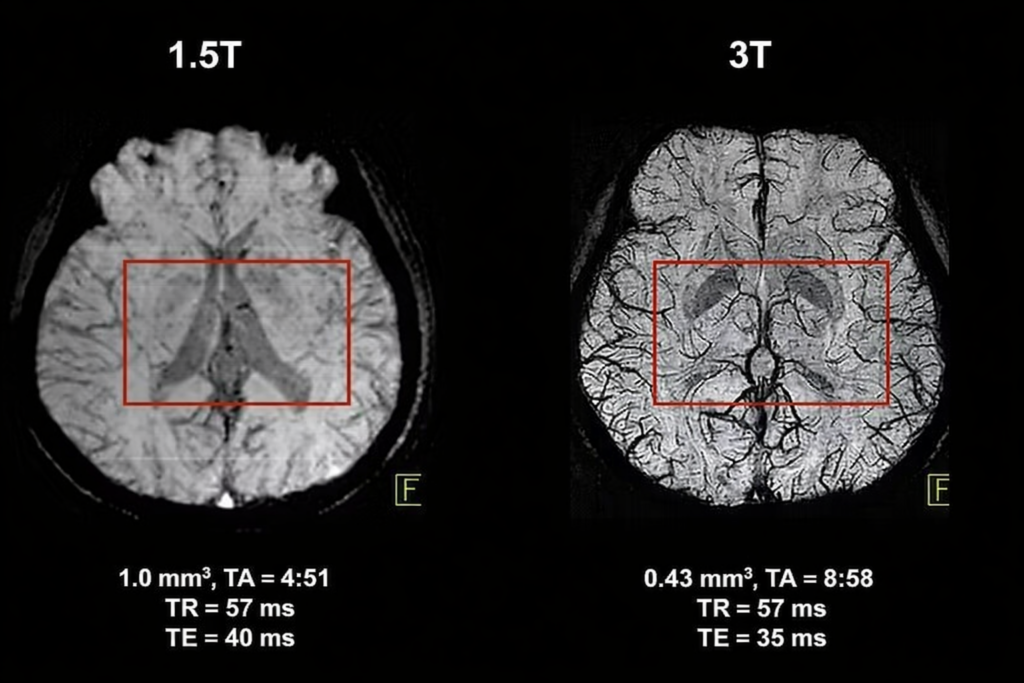

Какой аппарат МРТ лучше: 1,5 Тл или 3 Тл

Тесла (Тл) — это показатель мощности магнитного поля томографа.

Аппарат МРТ 1,5 Тл

Оптимален для большинства клинических задач:

- органы малого таза;

- позвоночник;

- суставы;

- контрольные и повторные исследования.

Преимущества: стабильное качество изображений, меньше артефактов, более комфортное обследование.

Аппарат МРТ 3 Тл

Используется по специальным показаниям:

- диагностика рассеянного склероза;

- эпилепсия;

- патология гипофиза;

- микроочаги и метастазы;

- исследование мелких сосудов.

3 Тл не является универсально лучшим вариантом и применяется тогда, когда требуется максимальная детализация.